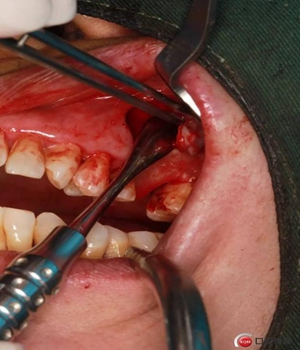

改良式外提升工具盒-外提 科貿(mào)嘉友收錄

大家好,我是梁老師的助理小依。由于梁老師每天手術(shù)檔期安排較滿,加上經(jīng)常出差講課,沒(méi)有時(shí)間整理病例 。為了方便大家更及時(shí)的了解梁老師最新手術(shù)動(dòng)態(tài),以后將由我為大家整理并推送梁老師最新經(jīng)典案例。案例文字旁白少,但圖片會(huì)盡量完整展示手術(shù)全過(guò)程,供大家學(xué)習(xí)參考。有任何問(wèn)題,可以留言,梁老師會(huì)親自為大家解答。感謝大家對(duì)梁老師的支持和關(guān)注!